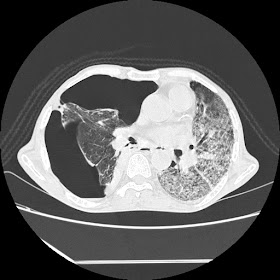

New HRCT images: